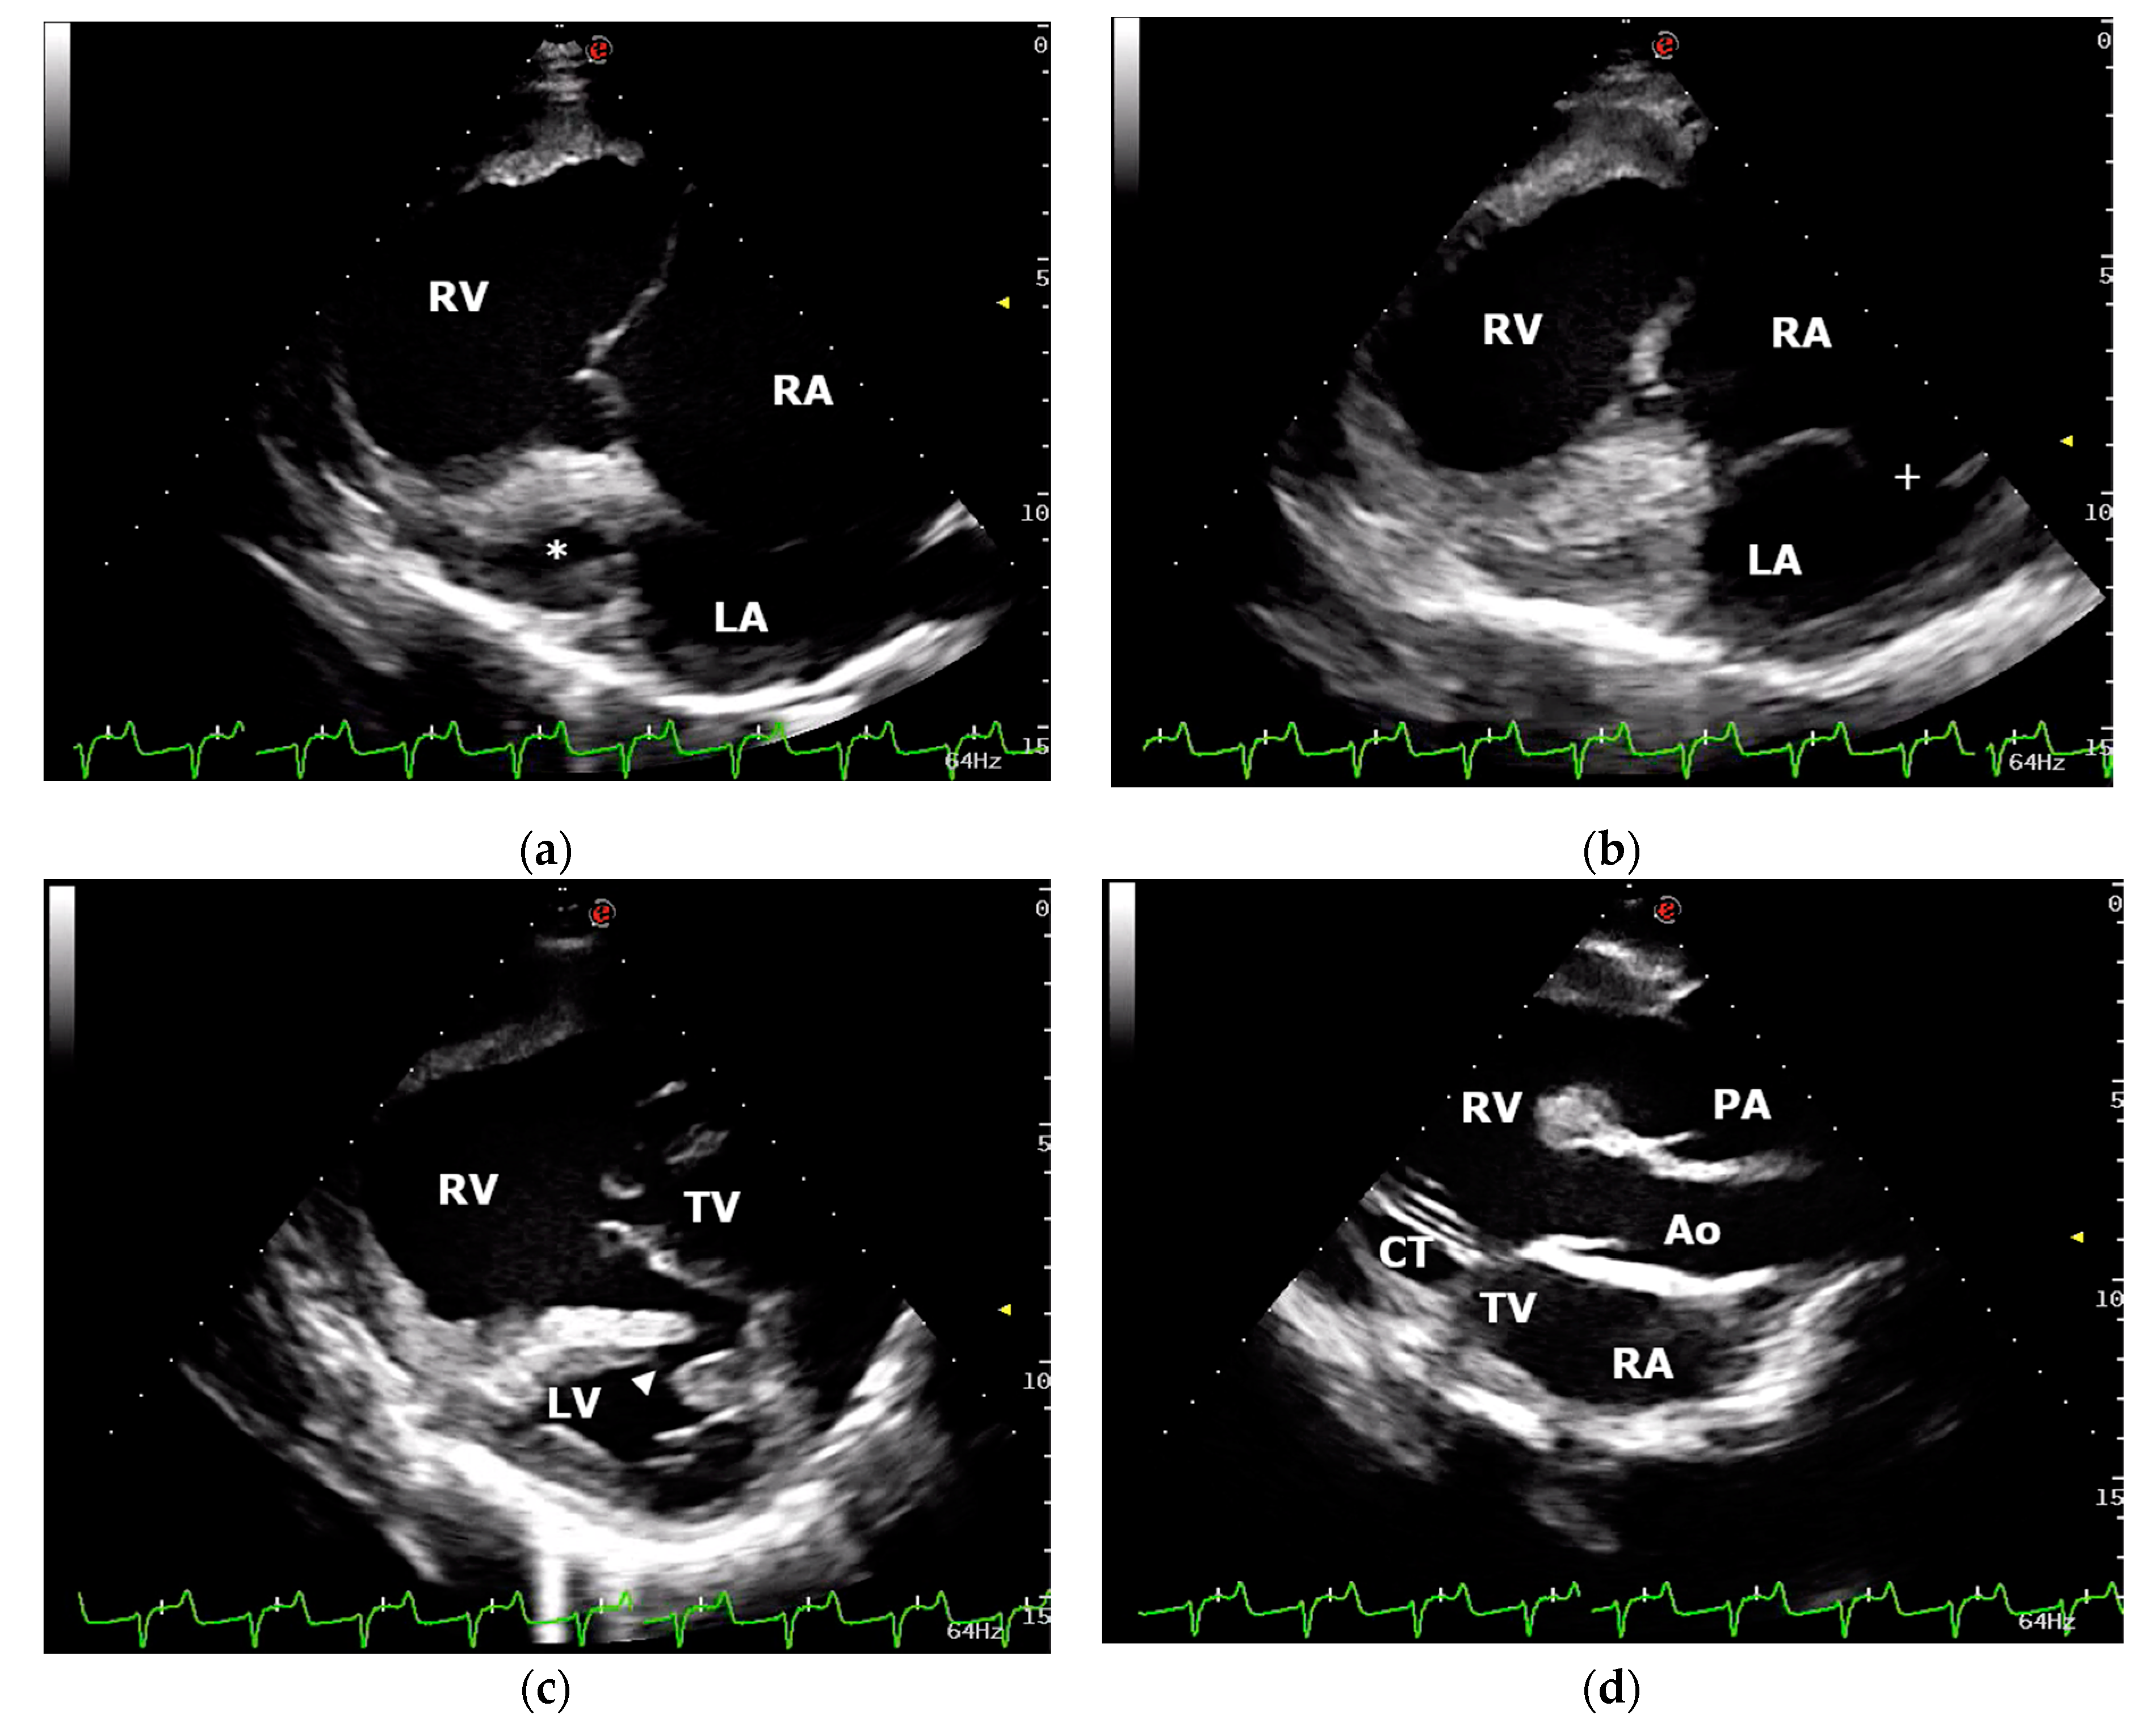

Transthoracic echocardiography was performed using an ultrasound unit equipped with multifrequency 1–4 MHz phased-array transducer (MyLab Class C, Esaote, Genova, Italy) and revealed severe dilation of the right ventricle and atrium with a markedly hypoplastic left ventricle (Figure 1). End-diastolic and end-systolic right ventricular (RV) diameters measured using the two-dimensional guided M-mode from the right parasternal ventricular short-axis view were 64.6 mm and 49.3, respectively. The RV fractional area change (FAC) was 51% (FAC = (RVAd–RVAs/RVAd) × 100, where RVAd/RVAs were RV end-diastolic and end-systolic area, respectively). The mitral valve apparatus showed a severely reduced mitral valve orifice. Interatrial septum presented an excessive mobility during the cardiac cycle and a large interatrial septal defect (16 mm) localized in the upper portion of the septum was visualized (Figure 1). Long- and short-axis echocardiographic views of the interventricular septum allowed the visualization of a small muscular interventricular defect (6 mm) localized in the dorsal part of the muscular portion of the septum (Figure 1). An oblique left cranial parasternal long-axis view revealed two great vessels leaving the right ventricle in parallel alignment with the tricuspid valve (Figure 1). The aorta and pulmonary artery were differentiated by identifying the coronary arteries arising from the aorta, and the left and right pulmonary arteries arising from the main pulmonary artery. Color-flow Doppler demonstrated severe tricuspid valve regurgitation and confirmed shunting of the blood through the interventricular and interatrial communications. Agitated saline contrast echocardiography performed through a catheter in the left jugular vein allowed visualization of the bubbles in the left atrium and ventricle. Moreover, bubbles were noted leaving the right ventricle via aorta and pulmonary artery simultaneously. A diagnosis of DORV with interatrial and interventricular septal defects was made. Based on the severity of the clinical signs, echocardiographic findings, and prognosis, euthanasia was chosen by the calf’s owner. After sedation, the calf was euthanized with barbiturate solution intravenously.

Figure 1.

Echocardiographic examination: (a) right parasternal, long-axis, four-chamber view demonstrating the severely dilated right atrium (RA) and ventricle (RV) and the markedly hypoplastic left ventricle (*); (b) right parasternal, long-axis, four-chamber view showing interatrial septal defect (+); (c) right parasternal, long-axis, four-chamber view optimized to visualize a small muscular interventricular defect (arrowhead); (d) left cranial parasternal, long-axis, oblique view showing aorta (Ao) and pulmonary artery (PA) leaving the RV in parallel alignment with the tricuspid valve (TV). LA, left atrium; LV, left ventricle; CT, chordae tendineae.